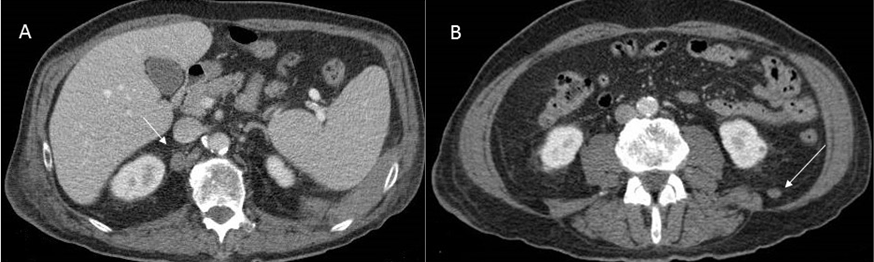

We report a case of a 64-year-old non-smoking male, who had had intermittent exposure to asbestos for three years. He had been undergoing treatment for hypertension. He presented with dyspnea on moderate exertion that had developed over several days, discomfort in the left hemithorax, and some intolerance to decubitus positions. The patient had a weight loss 10 kg in the last three months. A physical examination showed that he was conscious and lucid with normal coloring. Respiratory auscultation revealed hypophonesis in the lower half of the left hemithorax and right basal hemithorax. Hematological and hepatic findings were within the normal range. Tumor markers carbohydrate antigen (CA) 125, carcinoembryonic antigen (CEA), alpha-fetoprotein (AFP), CA 15-3, and CA 19-9 were shown to be within the normal range. Simple radiography of the posterior-anterior thorax showed bilateral pleural effusion with multiple nodular images in both hemithoraces (Figure 1). A contrast computed tomography (CT) scan of the thorax and abdomen revealed multiple bilateral pulmonary and pleural lesions, mediastinal lymphadenopathies (Figure 2), intra-abdominal implants (Figure 3), and a 56×40 mm polylobulated mass in the left buttock (Figure 4). A biopsy of the mass in the left buttock was made with an 18-gauge needle. Pathological study involved obtaining three cores of tissue measuring between 0.7 and 1 cm in length that were fixed in formalin. In the histological sections, we observed connective tissue infiltrated by epithelioid cells arranged in nests and trabeculae that showed atypia with hyperchromatic nuclei and prominent nucleoli. Occasional non-atypical mitosis was also detected (Figure 5). Immunohistochemical study revealed cytoplasmic positivity for keratins 5/6 and 7. Nuclear and cytoplasmic positivity was observed for calretinin, while nuclear positivity was detected for Wilms tumor 1 protein (Figure 6). Negative results were found for epithelial membrane antigen (Ber-Ep4), thyroid transcription factor-1 (TTF-1), protein suppressor p63, keratin 20, CEA, prostate-specific antigen (PSA), renal cell carcinoma (RCC), vimentin, common lymphoblastic leukemia antigen (CD10), S-100 protein, and CA 19.9. These results confirmed the diagnosis of metastasis of epithelioid mesothelioma. The patient passed away eight days later.

Figure 3: (A) Abdominal contrast computed tomography scan. Right retrocrural lymphadenopathy, and (B) Metastatic implant in the left perirenal space.